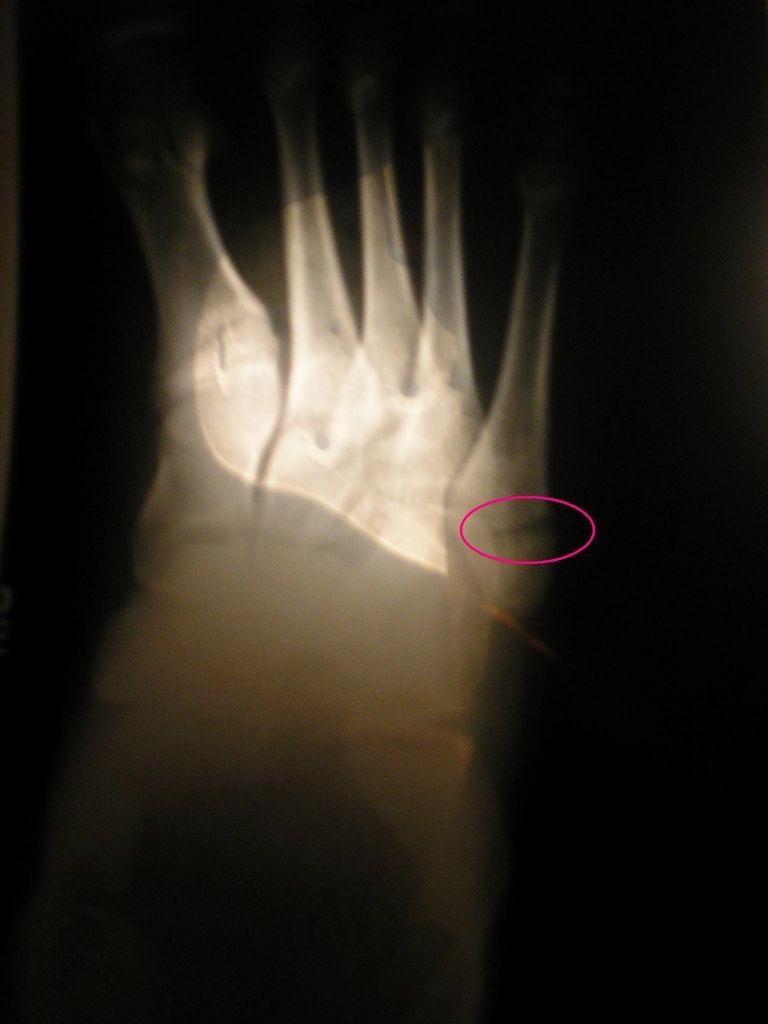

ONT .

Alla mellanfotsbenet's bilder

mellanfotsbenet